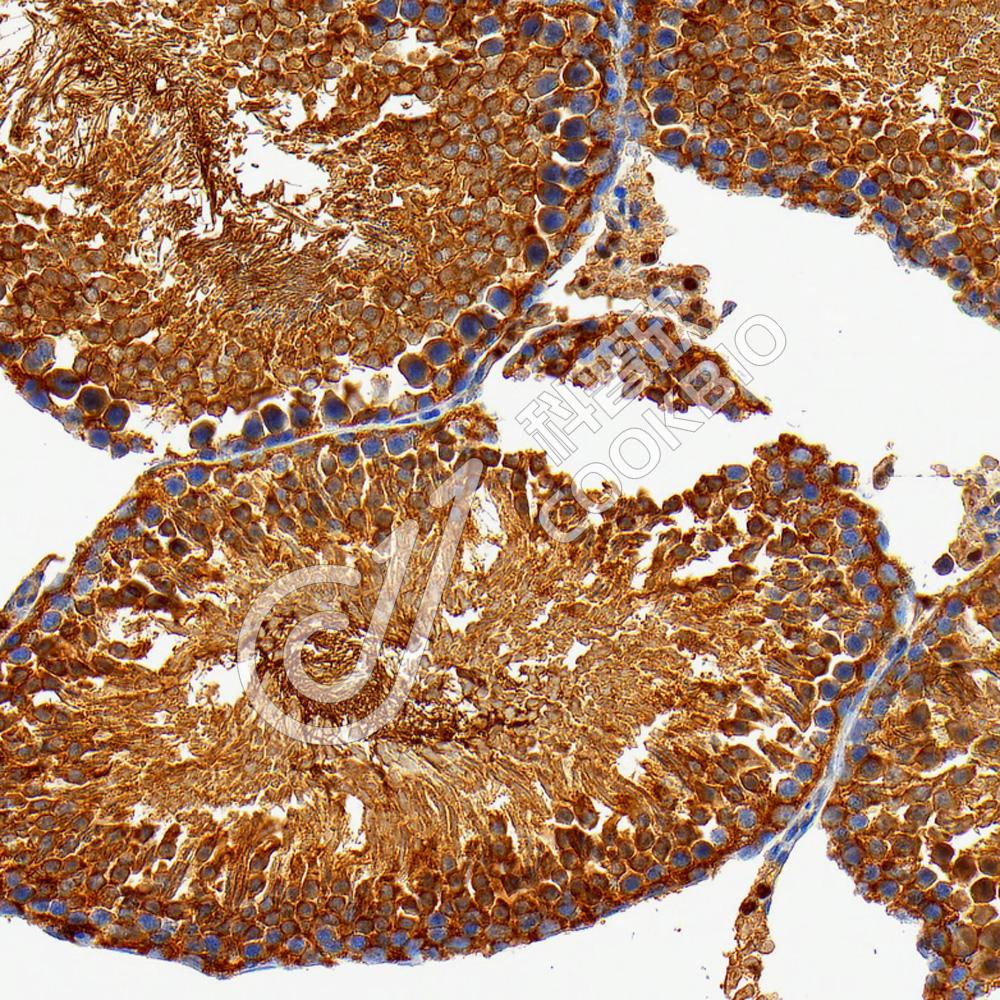

IHC检测PKA alpha蛋白(货号 K5450153).

样品: 小鼠睾丸, 4%多聚甲醛 (货号KSG1101) 固定12-24小时.

抗原修复: 柠檬酸抗原修复液(干粉, pH 6.0) (KSG1201), 高压锅均匀喷气计时2分钟.

—抗: 1: 3300稀释, 4℃ 孵育过夜.

二抗: S-vision免疫组化多聚二抗(山羊抗兔),即用型 (货号KB3906), 室温孵育20分钟.